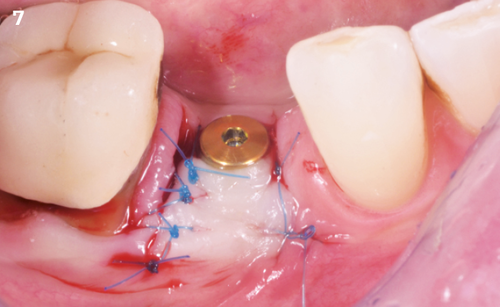

"After the extraction, I realized that the buccal wall was missing and I had to leave the membrane exposed. The regenerative potential of the site could be poor, so I decided to boost the biomaterials’ effect with polynucleotides and hyaluronic acid."

The Situation

The patient (45 years old, female, non-smoker, no previous pathologies) is referred for extraction of tooth 45 and immediate implant placement. The site showed an increased probing depth and a marked bone loss.